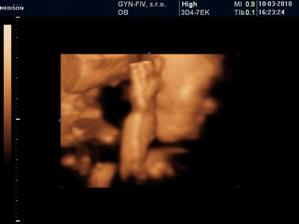

Ako rýchlo rastieme v brušinku 🙂

tatianka ďakujeme veľmi pekne 🙂 aj my sa z nich vytešujeme, kým je malinká v brušku a nevidím ju naživo